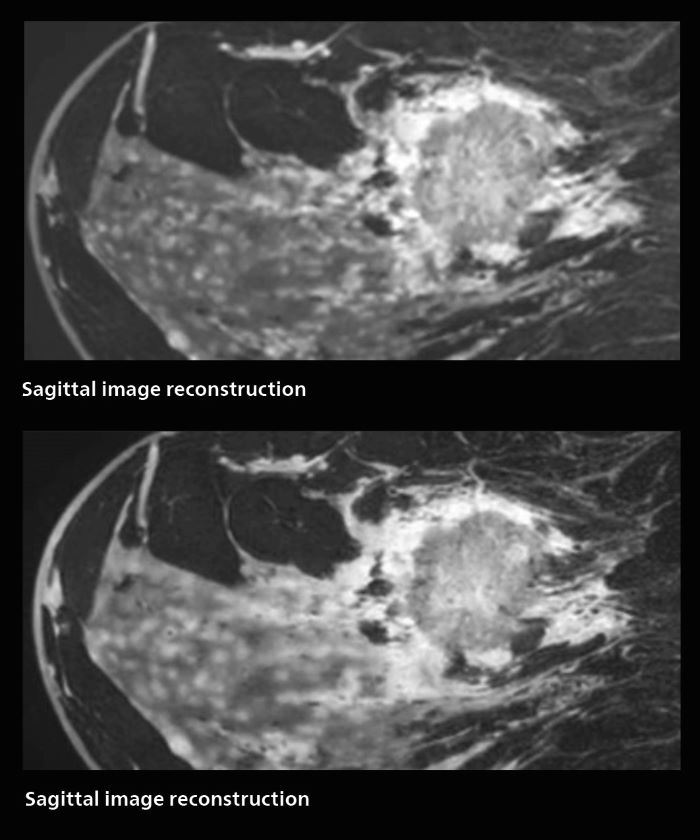

Fast, dynamic breast imaging for diagnostic confidence

Speed and high image quality are also important factors determining the diagnostic value of breast MRI. “When the spatial resolution is not high enough for making the diagnosis of breast cancer, a very difficult decision must be made,” says Dr. Katahira. “Since SmartSpeed now allows us to increase the resolution, we can often easily provide a confident answer. In the past with SENSE we used 1.2 mm isotropic voxels in breast imaging after contrast admission. With Compressed SENSE that is 0.8 mm. Now with SmartSpeed we can acquire 0.6 mm isotropic voxels and the images are so clear that even tiny details are clearly visible.”

“For example, we can now scan 20 consecutive, very fast dynamic images of the mammary glands with a single 3-second volume acquisition. This allows us to see how the blood flow is progressing in a very different way.”

“The use of SmartSpeed has considerably improved our breast cancer imaging, with higher temporal resolution, higher spatial resolution, and higher SNR compared to the past, when we were using just Compressed SENSE. In addition, the dynamic study is now more useful in diagnosis because the ultrafast dynamic scan can be taken every 3 seconds.”

3D MRI of breast cancer

Scanning was performed with two different voxel sizes. AI enabled volume MRI allows image reconstruction in other directions. Biopsy revealed invasive ductal carcinoma in this patient. Performed on Elition X.

Fast AI-enabled MRI of breast cancer: comparing 3D acquisitions with 0.75 mm and 0.6 mm isotropic voxels.

The hospital’s routine ExamCards for breast imaging include:

• ExamCard for 0.7 mm isotropic, 2:09 min, acceleration factor 7.5

• ExamCard for 0.6 mm isotropic, 3:37 min, acceleration factor 8